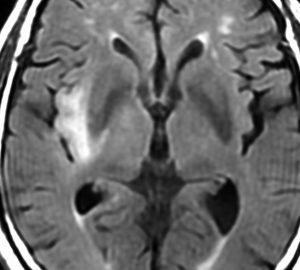

ガドリニウム増強される腫瘍の中心部に壊死があり,悪性神経膠腫としては腫瘍周囲浮腫が強すぎるように見えるので,リンパ腫 PCNSLに似た画像所見です。

脱髄性疾患であるtumefactive multiple sclerosisに画像所見も病理所見も類似することがあります。